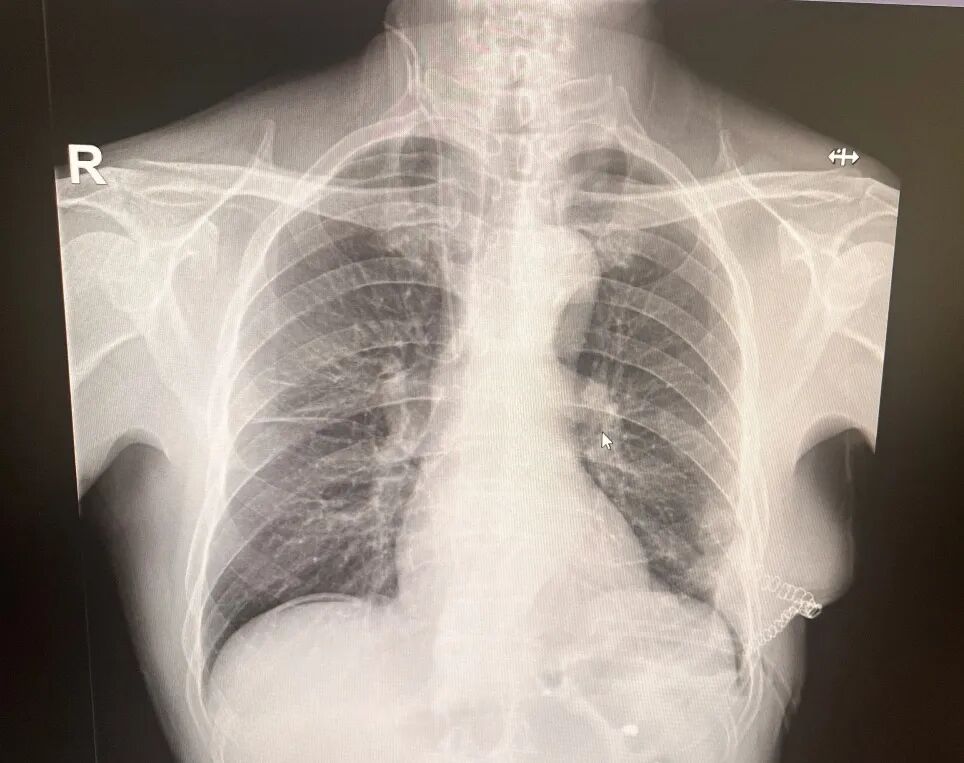

術(shù)前影像

輾轉(zhuǎn)來到市二院胸外科,孫振教授在細(xì)致追問病史時,捕捉到一個關(guān)鍵細(xì)節(jié):10年前,患者胸腹部曾被刀刺傷,當(dāng)時僅做了外部縫合,未深入排查內(nèi)部損傷。這一信息引起了孫振教授的高度警覺——很多陳舊性胸腹外傷雖表面愈合,卻可能遺留膈肌破裂的隱患,并隨時間推移發(fā)展為創(chuàng)傷性膈疝。腹部增強CT結(jié)果證實了這一判斷。